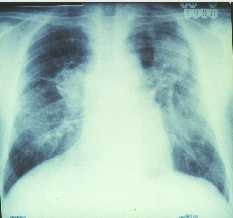

Conséquences du traitement médicamenteux

d’une tuberculose cavitaire très évoluée (années

80)